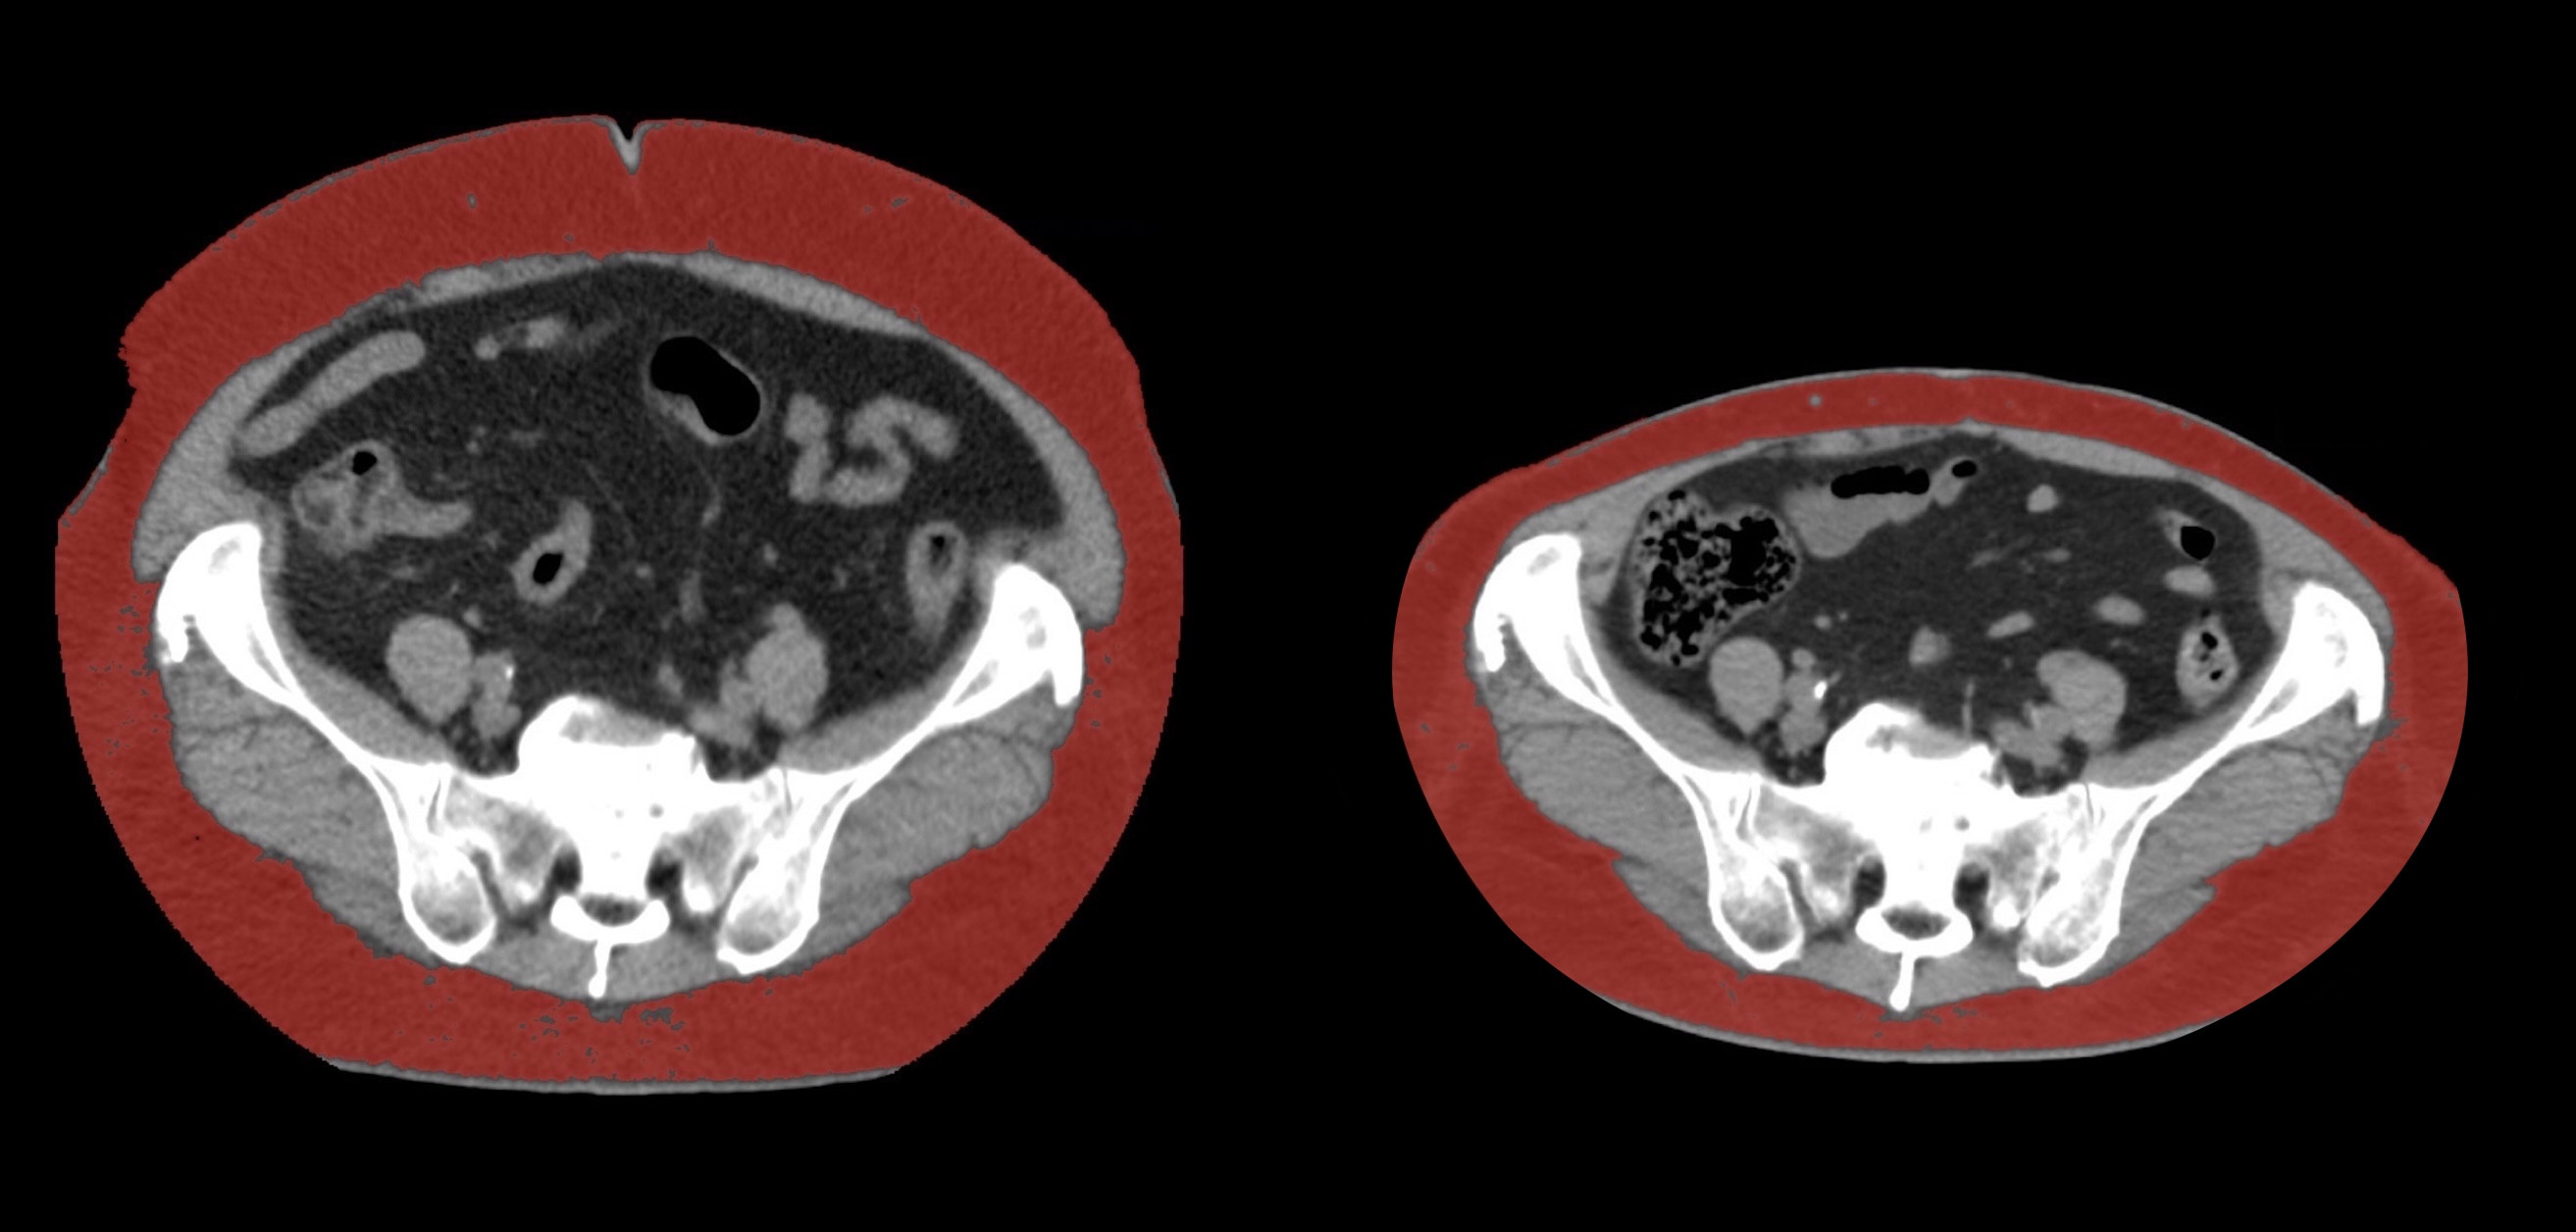

④

50代・男性(ご本人のご厚意で画像提供)

治療内容:チルゼパチド7.5mgの週1回自己注射による脂肪減少と脂肪肝改善

治療期間: 12ヶ月(52週)((用量は2.5mgから開始し最大で15mg。減量効果が得られる必要用量には個人差があります。))

費用:自由診療の場合は9900円(税込)×52(週)=514800円

想定されるリスク・副作用:下記に副作用を記載

※医療広告ガイドラインに準拠して表記

1:脂肪の減少

皮下脂肪の減少(赤色部分)